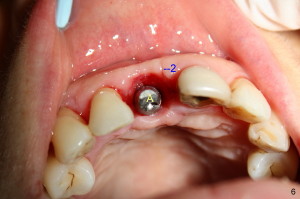

Fig.4 shows incision design for implant uncover (following osseous surgery in the upper right quadrant). The main incision is indicated by black line, lingual to the crest so that the buccal flap is more bulky. It is curved and festooned to create the future cosmetic buccal gingival margin. If the main incision is placed too lingual to expose the implant, one or two accessory incisions (red) can be made. After insertion of 4x6.5 mm non-shouldered abutment 3 mm post, PVS impression is taken. Fig.5 shows temporary crown in place (T) with two vertical mattress suture in the mesial and distal papillae. Two accessory incisions are approximated. Two weeks later, the temporary crown is removed. The accessory incision #1 has healed, while #2 is healing (Fig.6). The temporary crown helps form a nice socket around the abutment (A). Fig.7 shows the gingiva around the crown (to be cemented) with healing incision #2. Five months after crown cementation, the gingiva looks healthy.